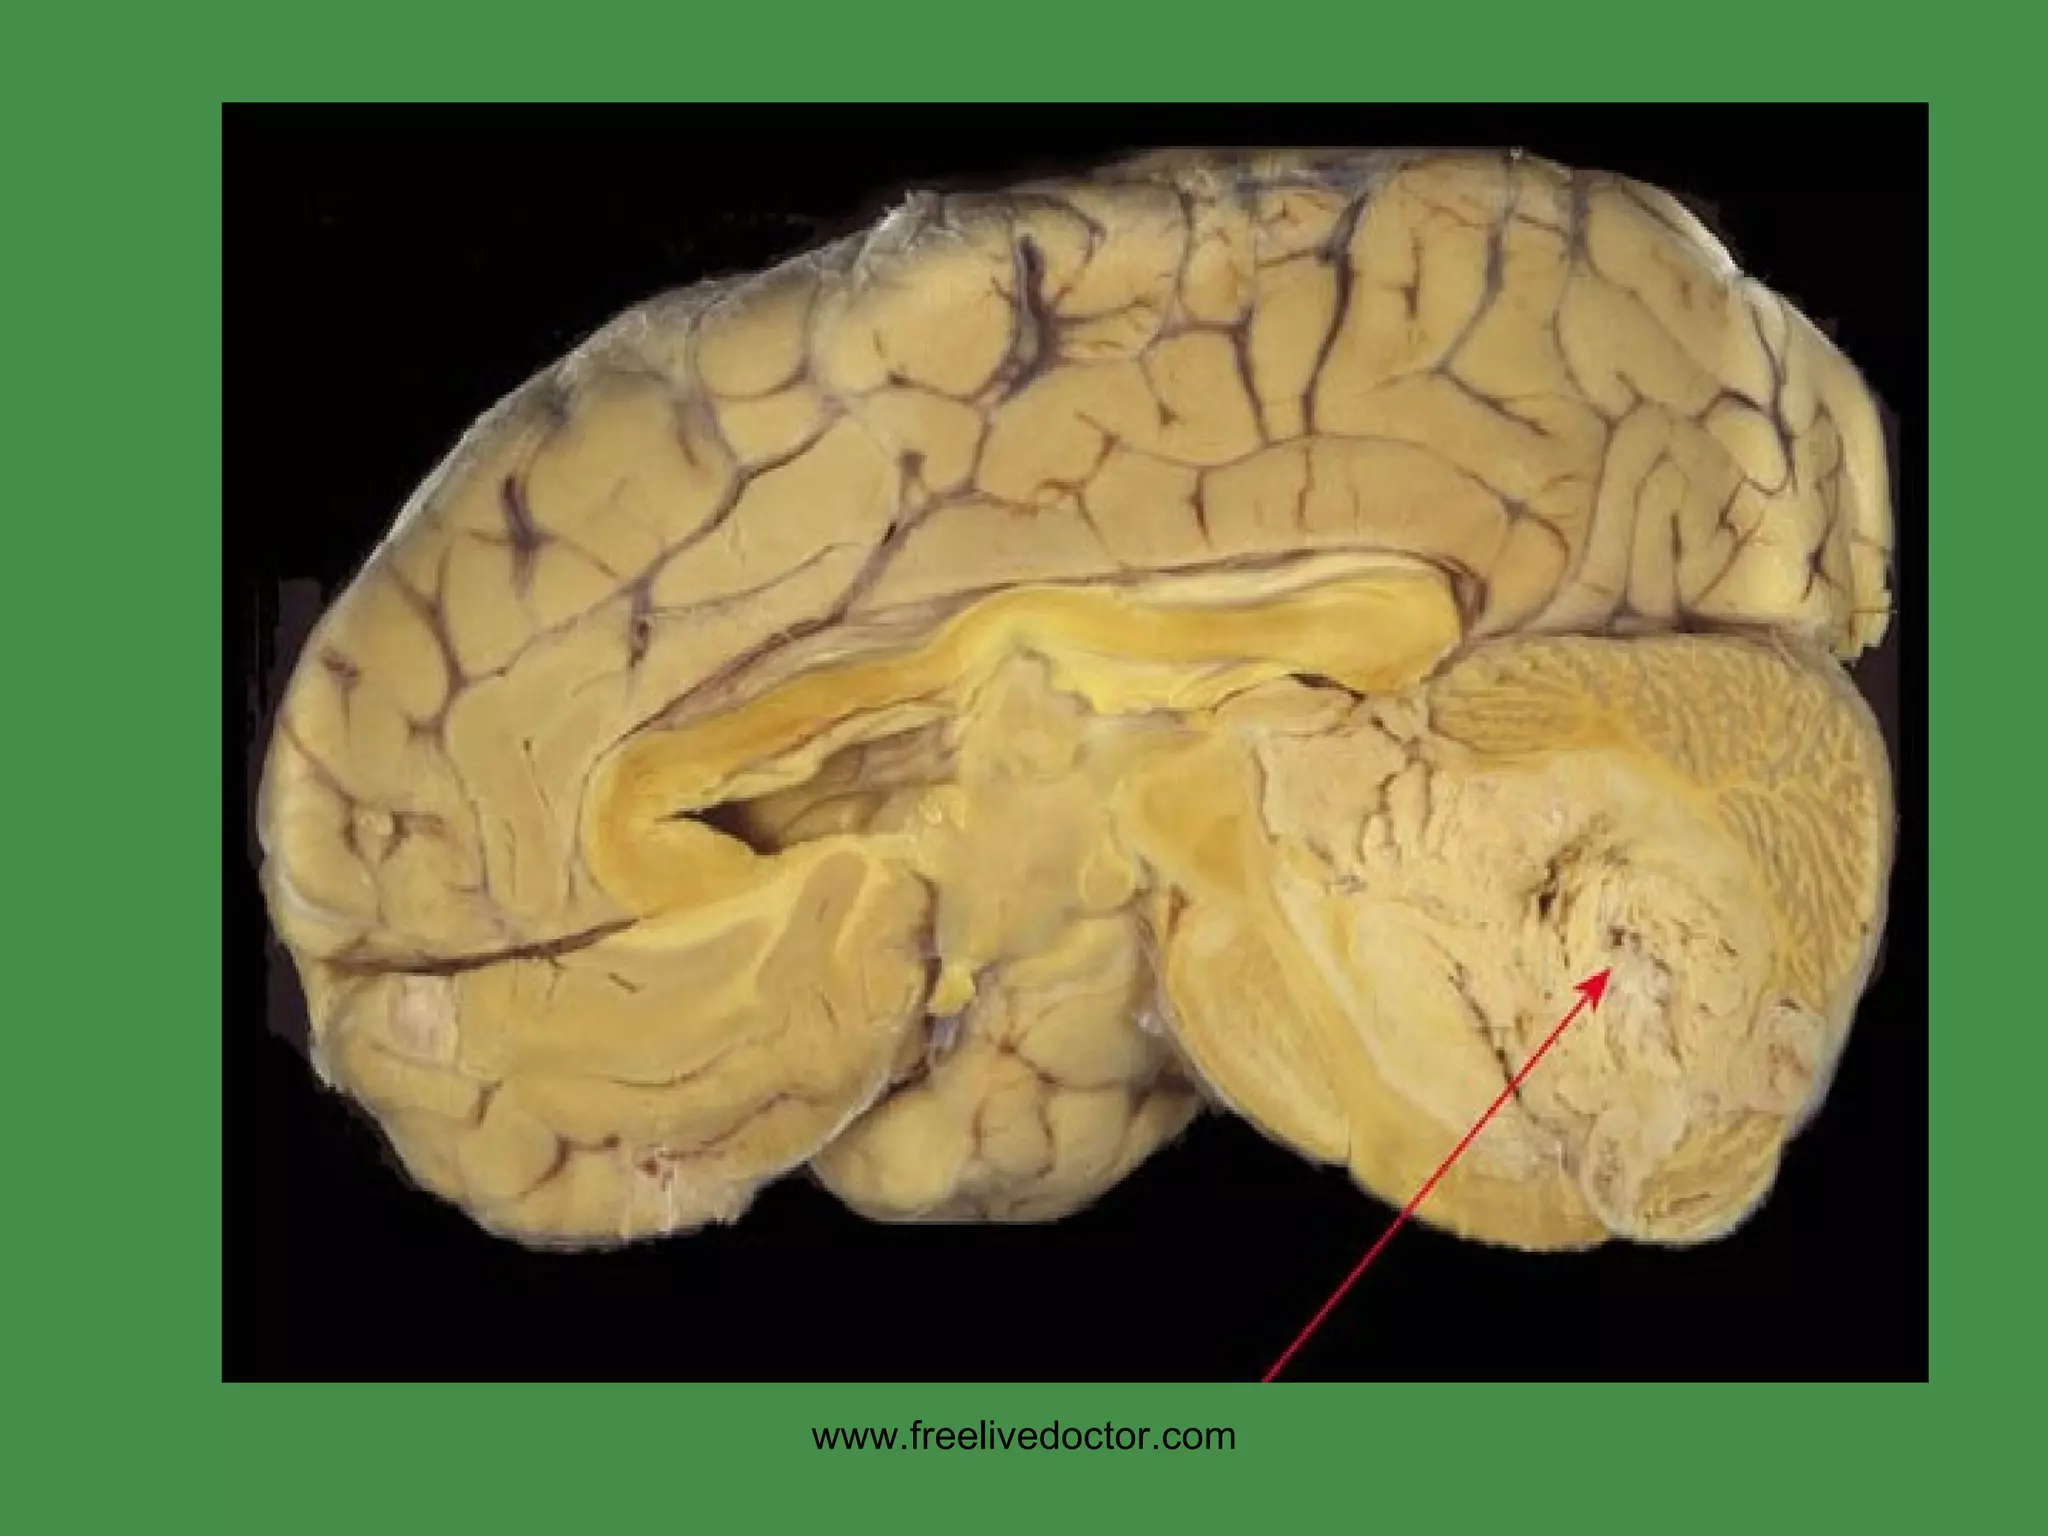

• #159 Any midline cerebellum tumor in a child is a medulloblastoma till proven otherwise!

• #160 Midline cerebellum tumor in a kid. What is it? Ans: medulloblastoma